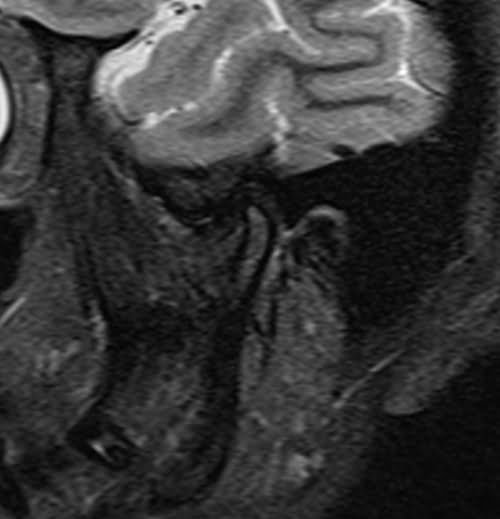

TMJ left side STIR images